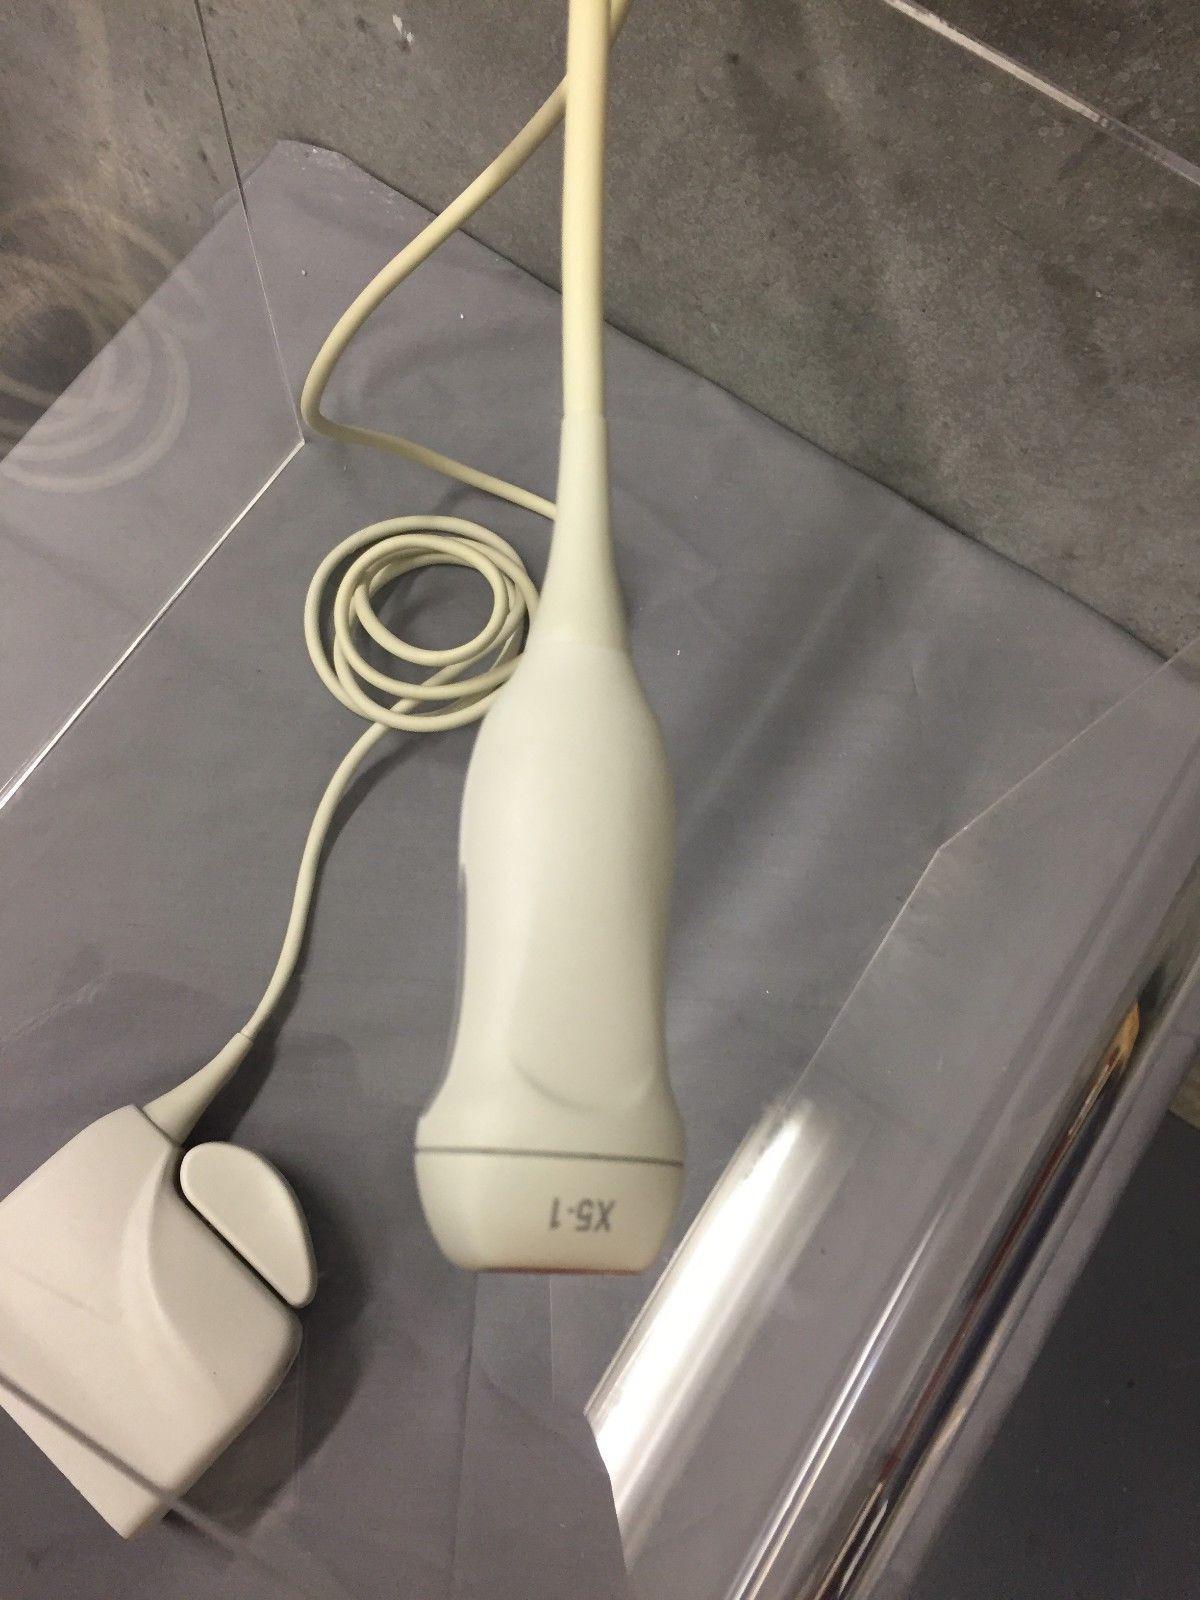

Philips X5-1 Explora Ultrasound Transducer

Sale price$ 45,572.30